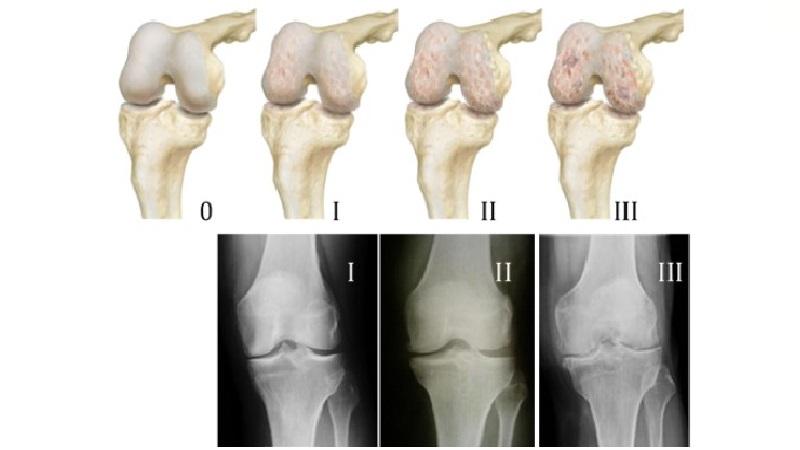

В течение многих лет болезнь прогрессирует, поэтому первые симптомы артроза могут быть едва различимы – боль в колене, беспокоящая во время физической активности, утренняя тяжесть в ногах и скованность.

В более поздний период артроза (2 стадия) симптомы проявляются более отчетливо – при движении сустава слышны хруст и треск, которые сопровождают болевые ощущения, в суставной сумке скапливается жидкость (выпот), заметно снижается функциональность коленного сочленения, невооруженным глазом становится заметна деформация.

Третья стадия патологии характеризуется сильным или полным разрушением хрящевой ткани, ограничением подвижности, болезненностью, которая не прекращается в состоянии покоя. Заметно становится изменение походки вледствие деформации коленных суставов, а также может наблюдаться метеозависимость.

Четвертый этап представляет собой полностью деформированное и нефункционирующее коленное сочленение, при котором суставная щель отсутствует, хрящ разрушен, кровеносные сосуды терпят сдавливание. В таком виде колено перестает сгибаться и разгибаться, человек утрачивает трудоспособность.